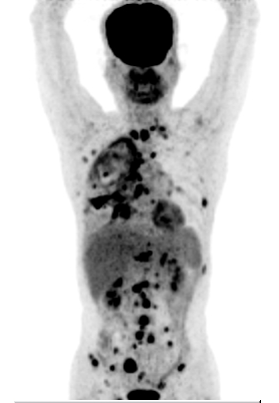

– Chụp PET/CT với F-18 FDG:

U thùy giữa phổi phải kích thước 23x32mm, tăng hấp thu FDG, max SUV=8,13, xâm lấn màng phổi. Ngoài ra nhu mô phổi phải còn một vài nốt mờ, nốt lớn nhất kích thước 16x10mm, tăng hấp thu FDG, max SUV=4,37.

Dày lan tỏa màng phổi phải, tăng hấp thu FDG, max SUV=5,43. Tràn dịch màng phổi phải dày 38mm.

Nhiều hạch trung thất, hạch nách, kích thước lớn nhất 15x13mm, tăng hấp thu FDG, max SUV=4,75.

Tổn thương xương đa ổ: xương sườn 2 bên, các đốt sống, xương cùng S1, xương chậu hai bên, xương đùi phải, max SUV=9,79.

Hình 3: Hình ảnh chụp PET/CT: u phổi phải di căn hạch, màng phổi, di căn xương đa ổ